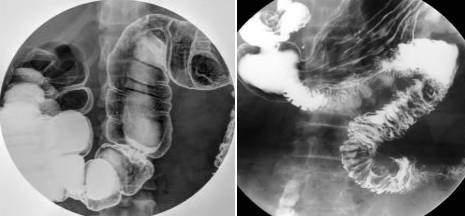

下消化道检查(钡剂灌肠):

在检查开始前,您的饮食可能会受到限制。为了清洗大肠,通常会使用泻药和/或灌肠的手段。检查开始时,你需要平躺在操作台上固定好,然后才会拍摄一系列X射线照片。这之后,医生会将液体钡通过放置在直肠内的小软管注入体内,这种液体会使人有微凉的感觉。然后医生会在操作台上将您变换不同体位以拍摄更多角度的图像。变换体位有助于钡在肠道中移动,因此可以在X射线上显影。每张照片拍摄时,你必须保持固定,屏住呼吸。

测试结束后,您可以去厕所将钡溶液从肠道排出。(这一过程可能需要几天才能全部排干净。在此期间,您的粪便可能会变干燥,变硬,颜色变浅。)

为了获得更清晰的图片,检查通常会进行“双对比”检查。该检查使用少量的高浓度钡液。钡进入体内后,肠道会被充入空气。这可能会导致饱腹感和不适感,以及产生排便的冲动。

上消化道造影:

在测试前8至12小时内,您可能会被要求禁食禁水。检查开始时,你需要平躺并固定在倾斜的操作台上,因为造影剂钡附着在你的食道和胃上,所以可以显影。在检查过程中,您可能需要多次服用钡餐。(在某些情况下,也会使用除钡之外的物质。)您可能还需要服用小苏打水以便在胃中产生气体。

有时也会在几小时后再拍摄更多照片,来观察小肠显影图像(钡从胃部移动到小肠需要一些时间),这被称为小肠造影。